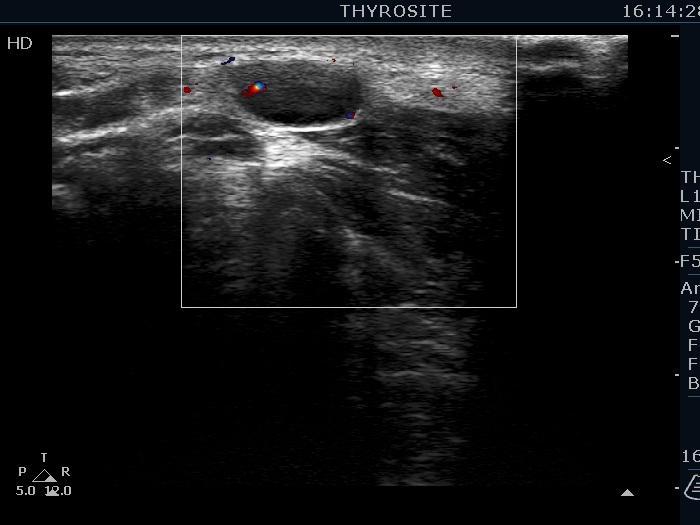

Lymph nodes - case 1131 (ultrasonographic picture 16)

Right lobe, longitudinal scan

Above and lateral to the left lobe, transverse scan, color Doppler mode. The lesion shows intralesional vascularity.